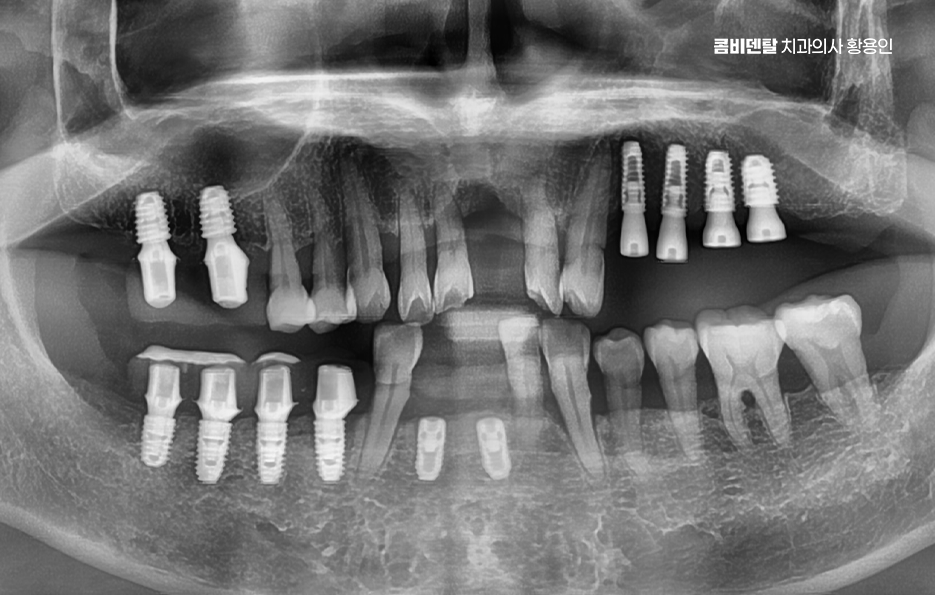

임플란트 치료를 앞두고 있는 상황에서 잇몸뼈 상태가 좋지 않은데도 불구하고 임플란트 뼈이식 안하면 어떻게 될지 궁금해하시는 분들이 많은데 실제로는 단순히 임플란트가 안 될 수도 있다는 차원을 넘어서 잘못된 시술이나 무리한 식립으로 인해 나중에 더 큰 부작용이나 재수술이 필요하게 될 수 있어서 뼈이식 여부는 단순히 선택이 아니라 치료의 안전성과 수명을 결정짓는 중요한 과정이 될 수 있는데요

임플란트는 턱뼈 안에 임플란트의 고정체(인공치근)를 식립해서 치아를 대신하는 구조로 이 고정체가 제대로 자리를 잡고 버텨주려면 최소한의 잇몸뼈 높이와 넓이, 골질이 확보돼 있어야 안정성이 확보되는 거예요. 그런데 이 뼈가 부족한 상태에서 임플란트 뼈이식 안하면 그리고 억지로 임플란트를 심게 되면 어떤 일이 생기냐면, 첫째로 임플란트가 제대로 뼈와 붙지 못해서 탈락하거나 흔들릴 가능성이 높고 둘째로는 식립 부위 주변의 잇몸이 꺼지면서 심미적으로도 부자연스러운 결과를 낳을 수 있어요

그렇다면 뼈이식을 언제, 어떻게 계획해야 하는지가 중요한데 첫 번째는 임플란트 식립 전 단계에서 충분한 영상 진단과 분석을 통해 뼈의 양과 질을 정밀하게 평가해야 하며 단순 파노라마 X-ray만으로는 확인이 어려운 입체적인 골량이나 신경과의 거리, 부비동 위치 등을 정확히 파악하려면 3D CT 촬영이 필수적이고 이를 통해 상악동 거상술이 필요한지 등을 판단할 수 있어요.

두 번째는 뼈이식을 단독으로 먼저 시행할 것인지, 임플란트 식립과 동시에 병행할 것인지를 결정해야 하는데 뼈 소실 정도가 심하지 않은 경우라면 동시에 진행할 수도 있지만, 뼈가 너무 얇거나 신경과 가까운 부위라면 3~6개월 정도의 치유기간을 두고 뼈이식만 먼저 시행한 뒤, 뼈가 자리 잡은 후에 임플란트를 식립하는 2단계 방식이 안전한 선택이 되는 거예요.

임플란트 뼈이식 안하면 대해서 결론적으로 말씀드리면, 잇몸뼈 상태가 좋지 않은데도 무리하게 임플란트를 진행하거나 뼈이식을 생략하게 되면 결국 치료 실패의 가능성이 높아지고, 수개월 또는 수년 후에 재수술이 불가피해지거나 더 큰 비용과 시간이 소요될 수 있는 상황으로 이어질 수 있으므로 단지 뼈이식은 무섭거나 부정적으로 느끼기 보다는 임플란트의 치료 원리 뿐 아니라 나아가 장기적으로 오랫동안 유지하며 사용해야 하는 자연치아의 대체 치료라는 점에서도 멀리 바라보고 치료에 임하시길 바라고 있어요